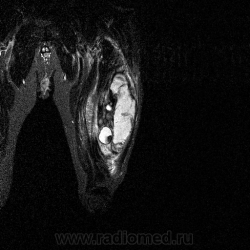

Ну вот аксиальные срезы, где то затерял =(

С учетом вашего опыта, мне кажется Вам и без дословной интерпретации МР-протокола будет все понятно.

Мой коллега в заключении указал о вероятней всего рабдолейомиосаркоме, если я ошибся то чуть позже поправлюсь.

Я тоже пока что в этом деле лось, но думаю дело поправимое, на днях улетаю С-Петербуг в МАПО(цикл КТ и МРТ), ну да ладно, что косается пациента то он ещё в 2007 году обращался по месту жительства к травматологу по поводу ушиба бедра с формированием гематомы, была назначена местная рассасывающая терапия, до 2009г. видимо ждали пока рассасется в декабре обратился к хирургу по поводу посинения и увеличения в объёме задней поверхности бедра, назначен гепарин в феврале был вскрыт абсцесс в этом месте, далее только в марте сподхватились по УЗИ-мягких тканей признаки образования, ну и открытая ножевая биопсия: Описание изменений, выявленных при микроскопическом исследовании: в материале фрагменты опухоли, представленной пучками вытянутых клеток с полиморфными гиперхромными, местами уродливыми ядрами. Определяется значительное количество митозов, встречаются поля некроза опухоли. При иммуногистохимическом исследовании опухолевые клетки экспрессируют виментин, отсутствует реакция на десмин, гладко-мышечный актин, S100. Патоморфологическое заключение: саркома мягких тканей, боее вероятно фибросаркома.